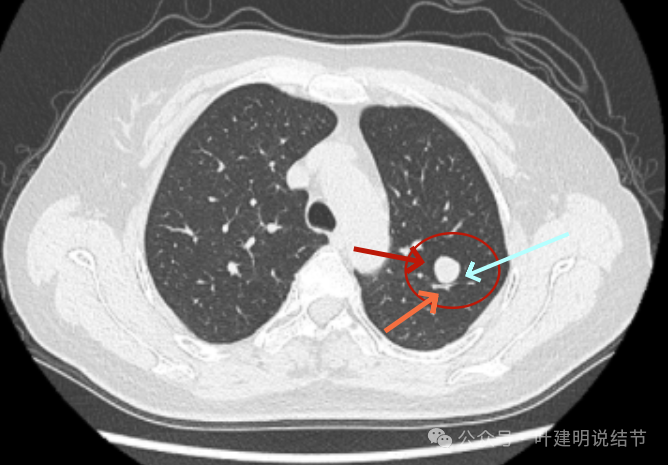

病灶出现,边缘区表面不是很光滑,似有少许磨玻璃成分以及边缘略显毛糙。

表面不是太光滑,中间的密度略显低。

血管贴得近,但没有牵拉或分支进入病灶,整体表面较为光滑。

与血管关系近,结节有膨胀感。

此层看与血管紧贴,没有间隙。局部有轻凹陷。

病灶明显感觉较为膨胀。

似见血管征,表面欠平滑,倾向浅分叶的样子。

边缘区密度不是太致密,有点像磨玻璃偏实的样子。

边缘区域混合密度的表现。